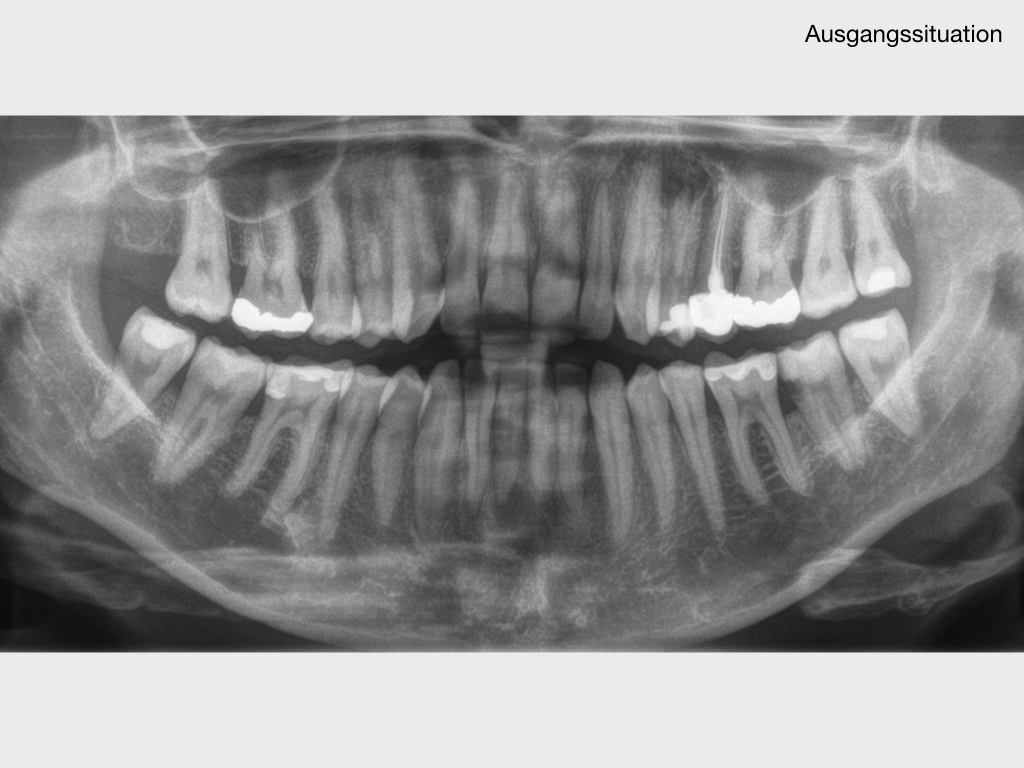

37 mit akuten Beschwerden